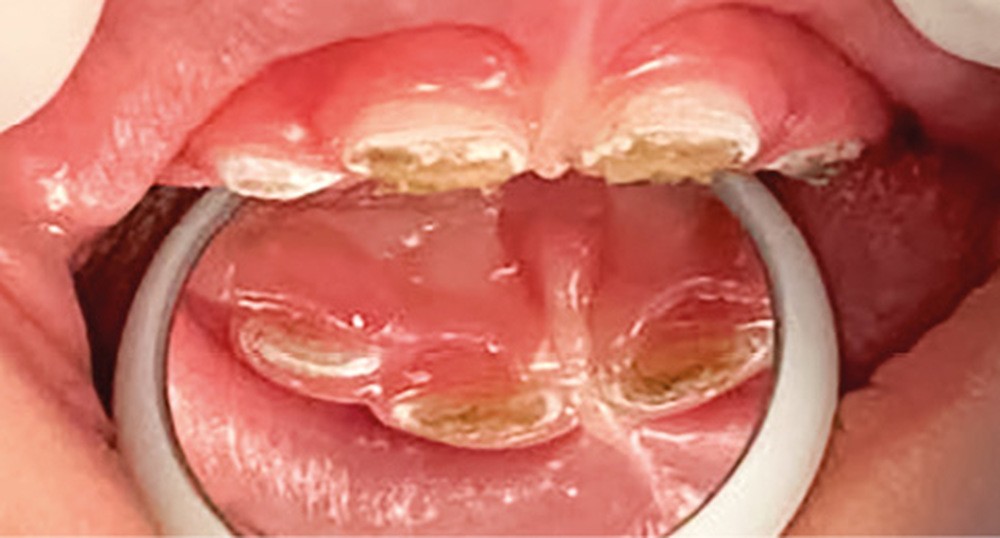

Dès l’atteinte d’une face de l’émail de la couronne dentaire, un traitement doit être proposé. Les traitements généralement conservateurs seront gradués selon la sévérité et l’activité de la lésion carieuse (fig. 1).